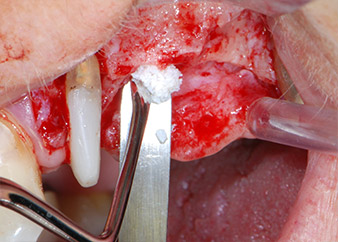

Prior to implant placement, and following verification of an intact Schneiderian membrane (Fig. 9), the internal sinus floor was augmented at both implant sites by means of xenogeneic bone substitute material (Bio-Oss, Geistlich Biomaterials) (Fig. 10).

CPITN-probe

Fig. 10: Introduction of xenogeneic bone substitute material into the implant osteotomy for internal sinus augmentation. The material was carefully condensed in an apical direction with the ball-ended CPITN probe (not shown).

Bone deficiencies around the implants, at the mesial aspect of tooth 27 and around the buccal root of tooth 24, were filled with xenogeneic bone substitute particles and covered with an absorbable collagen membrane (Bio-Gide, Geistlich Biomaterials) for GBR augmentation (Figs. 13 and 14).

Xenogeneic bone substitute material

Fig. 13: Xenogeneic bone substitute material was used to fill the remaining osseous defects …

absorbable collagen membrane

Fig. 14: ... which was then covered with an absorbable collagen membrane. The grayish-pink structure between the elevators at the top margin of the picture represents interproximal papillary tissue.